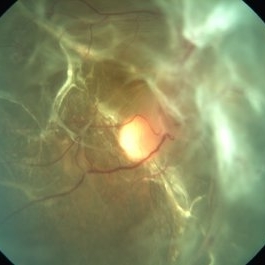

Morning Glory Syndrome

Sep 20 2014 by Mehul A Shah

A 4-year-old girl presented with complaint of exotropia, on examination she was found to have this picture.

Photographer: Drashti Netralaya,Dahod

Imaging device: Zeiss ff450

Condition/keywords: congenital anomaly